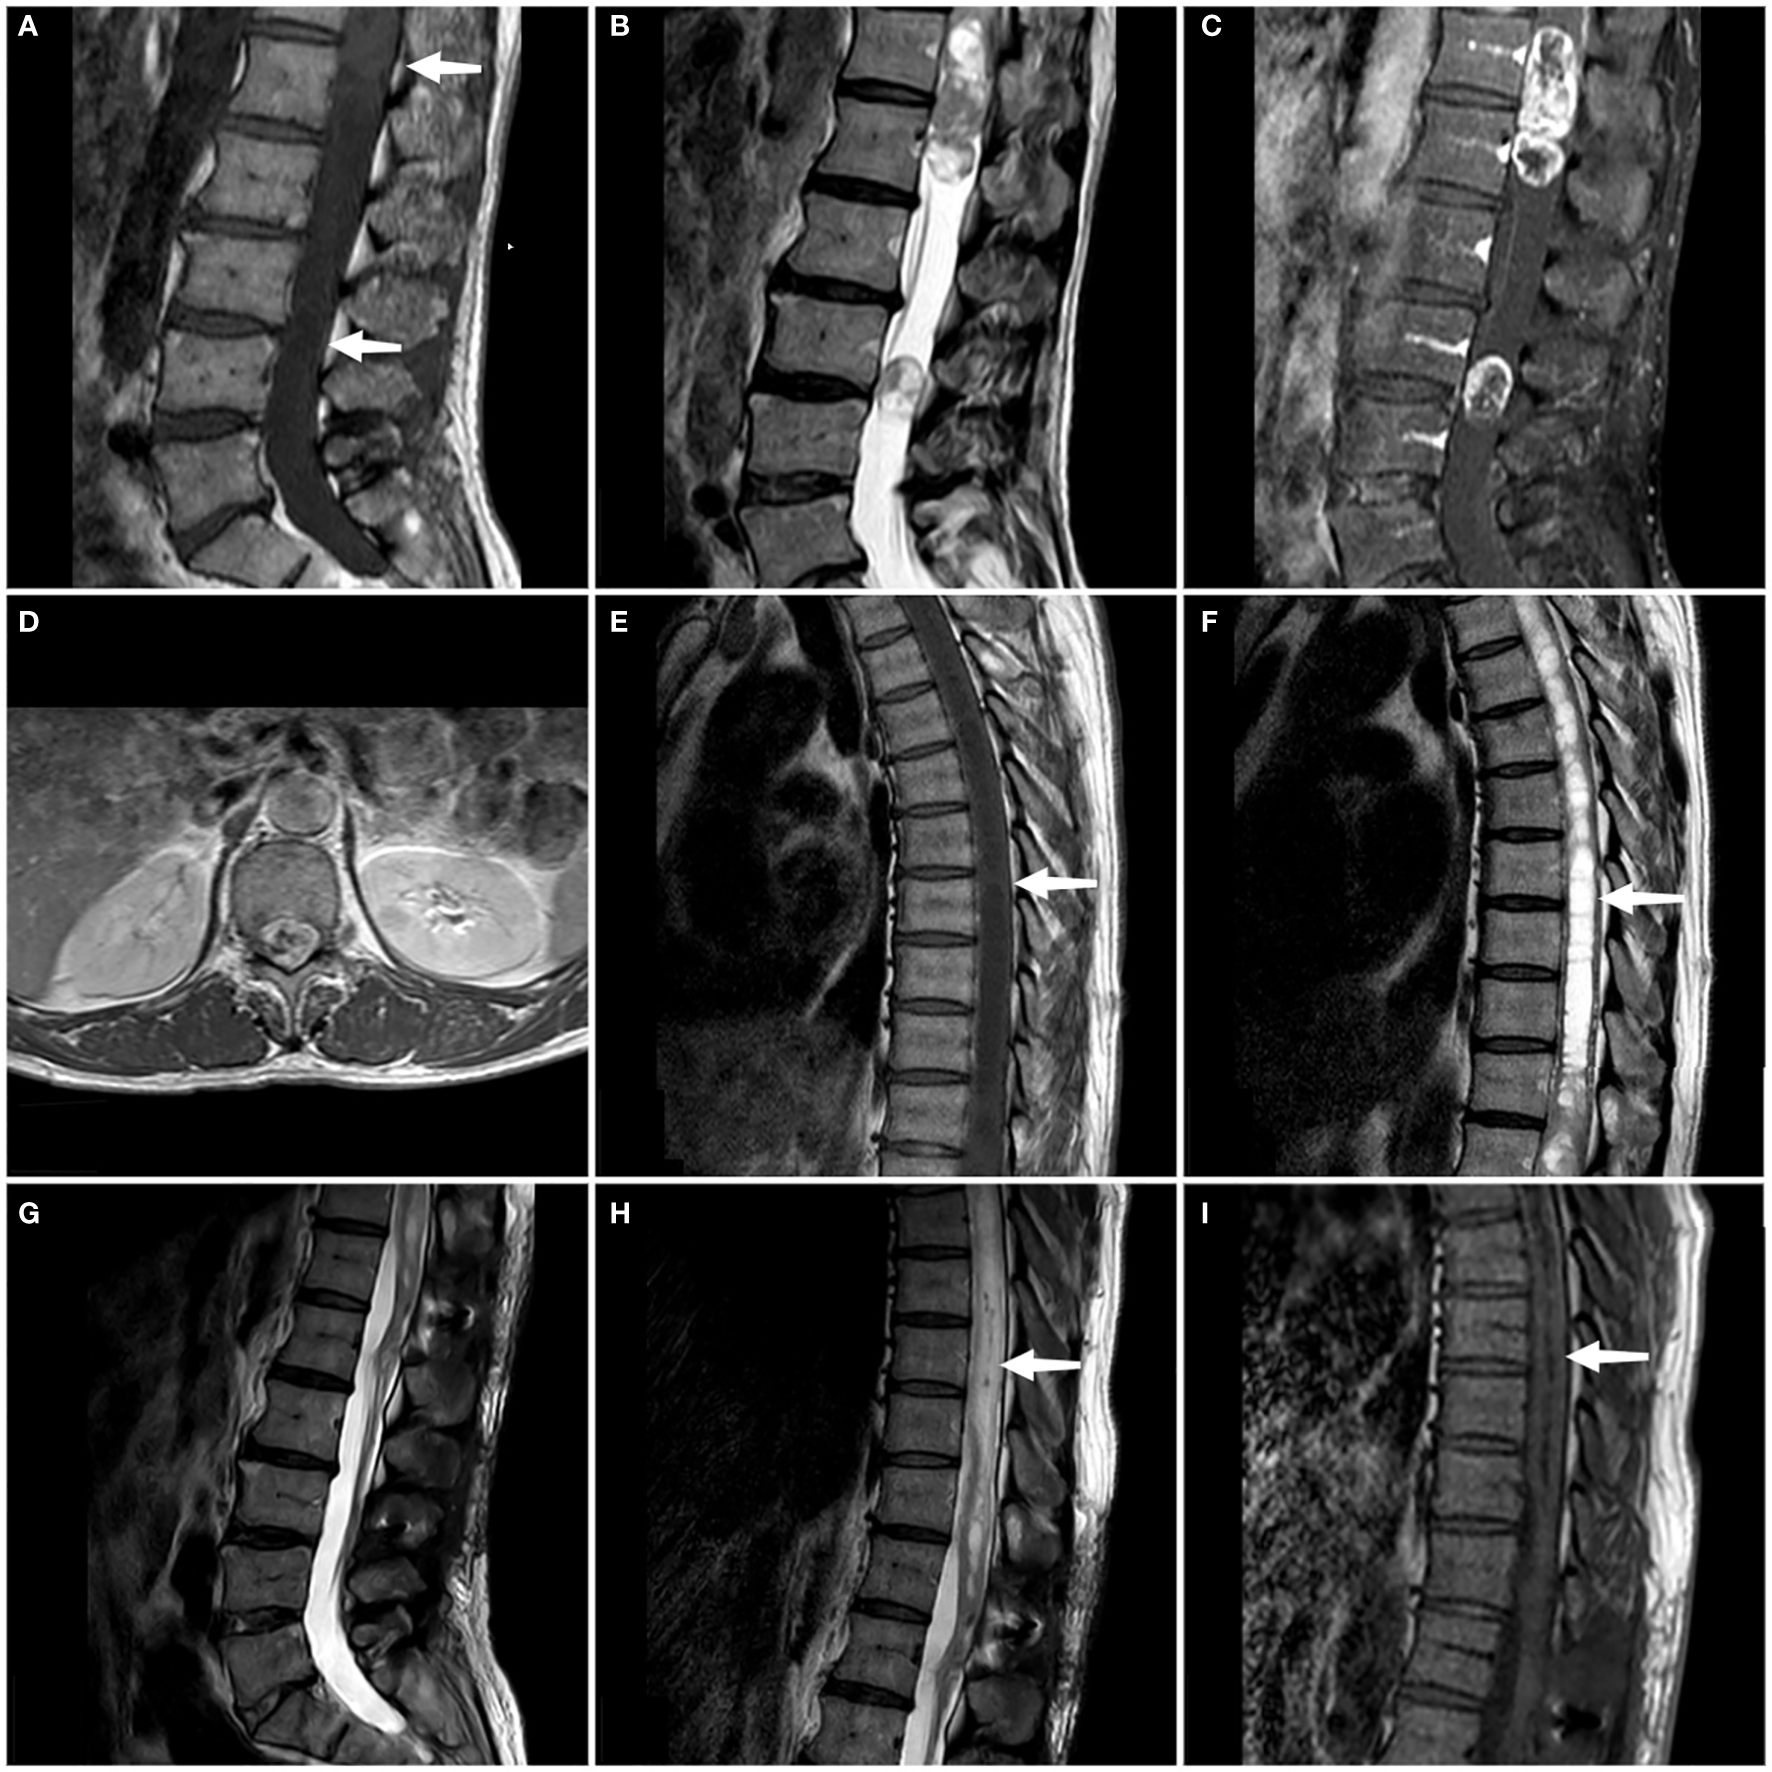

We conducted a comprehensive MRI scan of the patient’s entire spine, which included T1-weighted imaging (T1WI), T2-weighted imaging (T2WI), and enhanced scanning following the injection of a contrast agent. The tumors showed mixed signals on MRI plain scan and heterogeneous enhancement on enhanced MRI.MRI examination showed two tumors at L3 level and T11-L1 level respectively, measuring 8 × 8 × 10 mm and 24 × 54 × 20 mm. At the same time, syringomyelia at T4-T10 level appeared above the tumor at T11-L1 level (Figure 1). Based on the patient’s clinical manifestations and MRI examination, the preoperative preliminary diagnosis was schwannoma or ependymoma. Other differential diagnoses included glioma, astrocytoma, calcified tuberculoma etc.

Figure 1

On the sagittal T1WI sequence, iso-signal occupying lesions (at the white arrow) are discernible separately within the T11-L1 segment and the L3 segment (A). On the sagittal T2WI sequence, both tumors exhibit mixed signals (B). Enhanced T1WI scans in both sagittal and axial planes reveal significant and heterogeneous enhancement of both lesions (C, D). A persistent intramedullary abnormal signal at T4-T10 was seen above the lesion (at the white arrow), showing hypointense on the T1WI and hyperintense on the T2WI (E, F). Follow-up MRI at 3 months confirmed complete tumor removal with no recurrence (G). Sagittal T1- and T2-weighted thoracic MRI images reveal a marked reduction in syringomyelia compared to preoperative findings (white arrow) (H, I).

At the time of discharge, the patient’s condition was significantly better than that on admission, the weakness of the right lower limb was significantly relieved, and he could basically walk normally. He still had weakness of the anal sphincter and difficulty in bowel and defecation. The lumbar incision healed well. Physical examination showed grade 5 muscle strength in the right lower extremity and Babinski signs were negative. Three months later, the patient’s bladder and stool function was significantly improved compared with that before surgery, and he could walk completely independently. MRI reexamination showed that the tumor was completely removed and no recurrence was observed, and syringomyelia significantly shrank (Figure 1). During the one-year post-operative telephone follow-up, the patient is currently able to walk normally, with urinary and bowel functions having largely returned to normal, and the preoperative symptoms have essentially dissipated.The treatment timeline is shown in Figure 3.